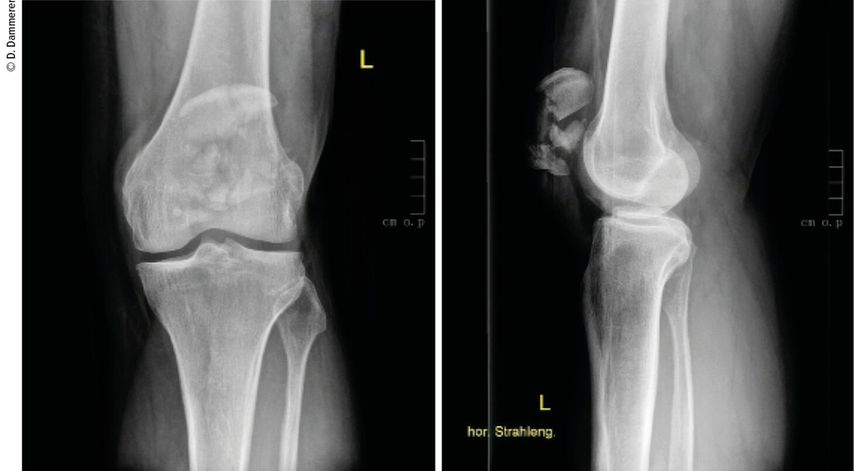

Die Diagnostik erfolgt mittels konventioneller Röntgendiagnostik (antero-posterior, seitlich) und bei Bedarf ergänzender Computertomografie (CT) bei multifragmentären Frakturen oder unklaren Frakturausläufern.

Die Durchführung einer ergänzenden CT spielt gerade im Hinblick auf unklare Frakturausläufer eine entscheidende Rolle.5 So konnte in Studien gezeigt werden, dass das Frakturausmaß und insbesondere die Mitbeteiligung des distalen Pols bei konventioneller Röntgendiagnostik oft unterschätzt werden.6 Lazaro und Kollegen untersuchten, wie eine ergänzende CT-Untersuchung die Therapie von 4 Fachärzten beeinflusst. In 66% der Fälle wurde nach einer ergänzenden CT-Beurteilung die Klassifikationszuteilung der Patellafrakturen adaptiert und der Behandlungsplan änderte sich in 49% der Fälle. In 88% der Fälle war der distale Patellapol mitbetroffen, was nur in 44% der Fälle auf Röntgenbildern gesehen wurde.

Abb. 1: Eine komplexe Mehrfragmentfraktur der Patella ergibt die Indikation zur operativen Versorgung